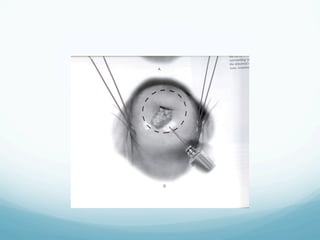

Sharp Conization

—  One of the oldest techniques

—  Recommended for women with suspected

microinvasion and AIS

—  The margins of the cone are plotted colposcopically

using acetic acid or Lugol s solution

—  The configuration of the specimen is based on the

extent of disease

—  Complications include: bleeding (immediate or

delayed), cervical stenosis, cervical incompetence